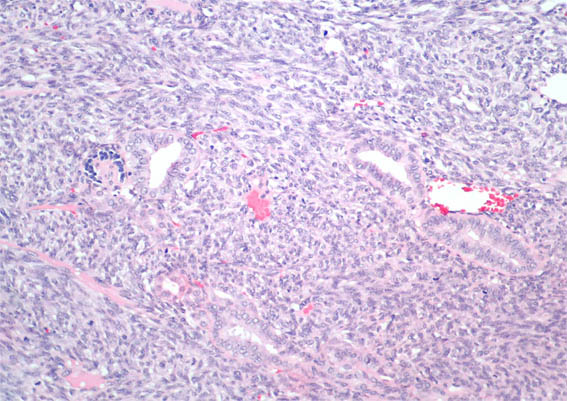

Figure 5. H&E, X200.